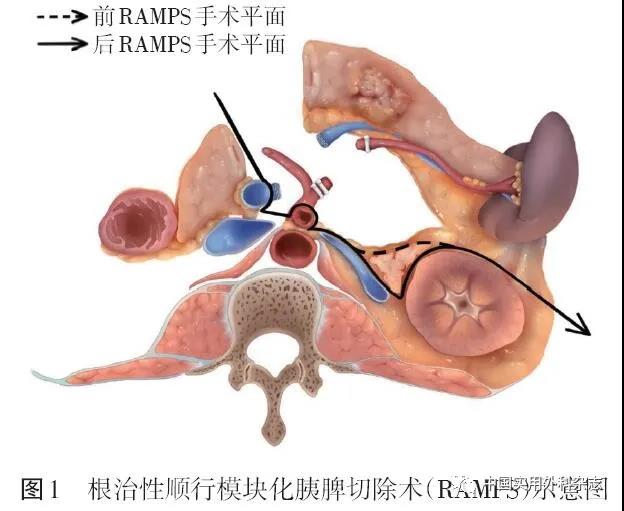

胰腺癌的发病率在世界范围内呈持续上升态势。2021年统计数据显示,在美国所有恶性肿瘤中,胰腺癌新发病例男性居第10位,女性居第9位,占恶性肿瘤相关病死率的第4位。...